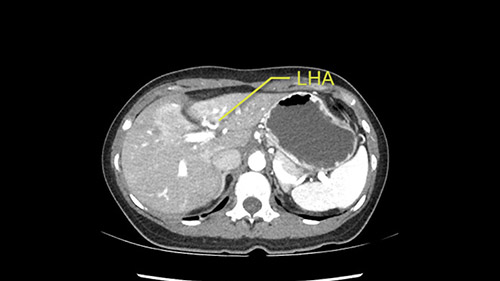

Inflow is not usually an issue except if there are as a replaced or aberrant left hepatic artery. In which case you’d be careful when you mobilize the left lateral segment.

So I have to say that I would do this open, not laparoscopically because of the size of the tumor itself. Upper abdominal incision. Almost certainly, we’d be able to flip this very exophytic lesion up. Intraoperative ultrasound will show the relationship of the tumor and the left portal vein but the dissection at the base of the liver, as I look at things here, I can see the left hepatic artery which sneaks up to the left of the portal vein, should be out of harm’s way so I can take the Segment 2-3 left hepatic artery. The left portal vein is somewhat compressed. But by the time you pull the liver up a bit, you’ll be able to pull that left portal vein out to length and get a good margin on it.

So what I would do, I would find out most probably this mobile tumor, it would not be a problem to explore the hepatic pedicle and check, find out no other invasion around the pedicle; and we have to check the left artery as well. The right side artery is fine. If there is any replaced arteries, we have to know during the case, may be or may not be preserved. It would not be a big problem actually because the right side will feed it.

The second is the left hepatic artery. The tumor is displacing the arterial system. So one of the important points which we need to see intraoperatively is to identify and preserve the right artery very carefully and identify the left hepatic artery for ligation.

RHA, Sg4 artery not involved in tumor

LHA feeding branches to tumor

So in planning for this operation, as I look at the scans, I first visualize the arterial phase and I can see that there’s are a lot of big feeding arteries to this large tumor. Likely all the right side vessels feeding the right side of the liver: right hepatic artery and likely the Segment 4 artery are spared from the tumor. It’s likely the left hepatic artery is ramificating and giving feeding arteries to this tumor. It certainly looks like a large mass that its compressing other structures like the cava, the pancreas, the stomach; but I think there’s a plane and we can see that better in the venous phase. There’s a plane of separation between the gallbladder, the pancreas, the cava, that this tumor is abrupting but likely not invading. Usually, these masses actually don’t invade at that level and basically are pushing the tissues and once you open, you’re able to separate the tumor. Sometimes there’s some adhesions but you can actually separate and there’s usually no invasion.